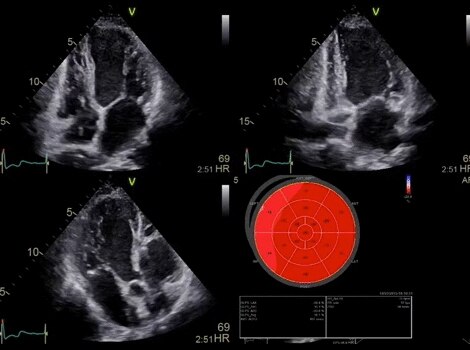

AFI Stress

Quantify wall motion at all stress levels. Integrated as part of a stress exam, AFI Stress protocols acquire standard apical 2D views and quantify both longitudinal segmental and global strain for contractility assessment at each stress level. Bulls-eyes from the different stress levels can then be easily compared.

Vivid Family Cardiac Ultrasound

Automated quantification tools such as AFI 2.0 with EF, Auto LVQ, Auto LAQ and Cardiac Auto Doppler for patient follow-up.